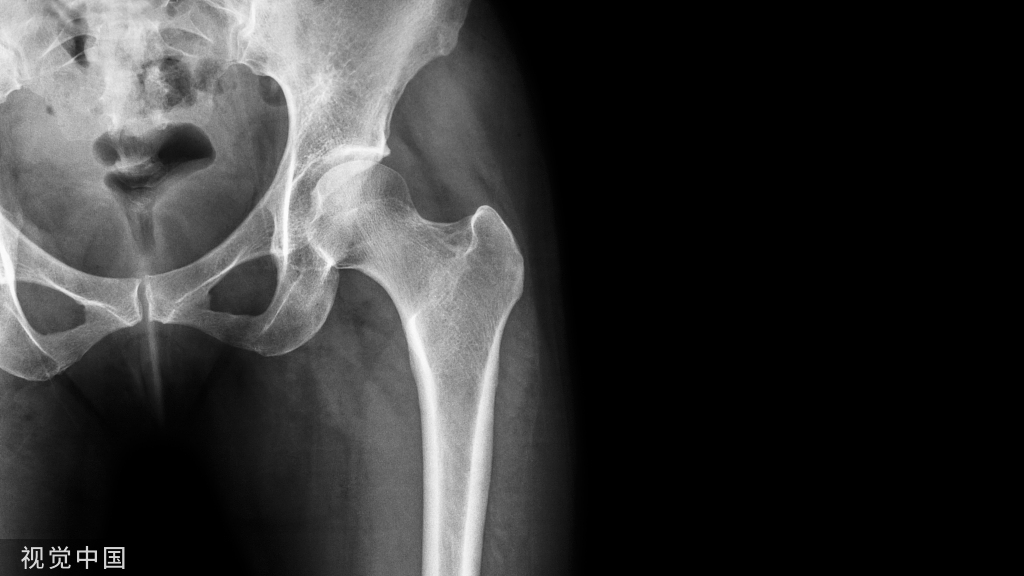

椎间盘解剖

椎间盘是连接相邻两个椎体的纤维软骨盘,由两部分组成,周围部为纤维环(Anulus fibrosis)是由数十层环状及放射状的胶原纤维及弹性纤维交织而成按同心圆排列的致密组织,富于坚韧性,将各椎体紧密牢固的连接成一体,保护髓核并限制髓核向周围突出。

图 1 正常椎间盘示意图,椎间盘由周围的纤维环和中心的髓核组成

图 2 正常椎间盘在相邻两个椎体之间,周围不超出椎体的边缘